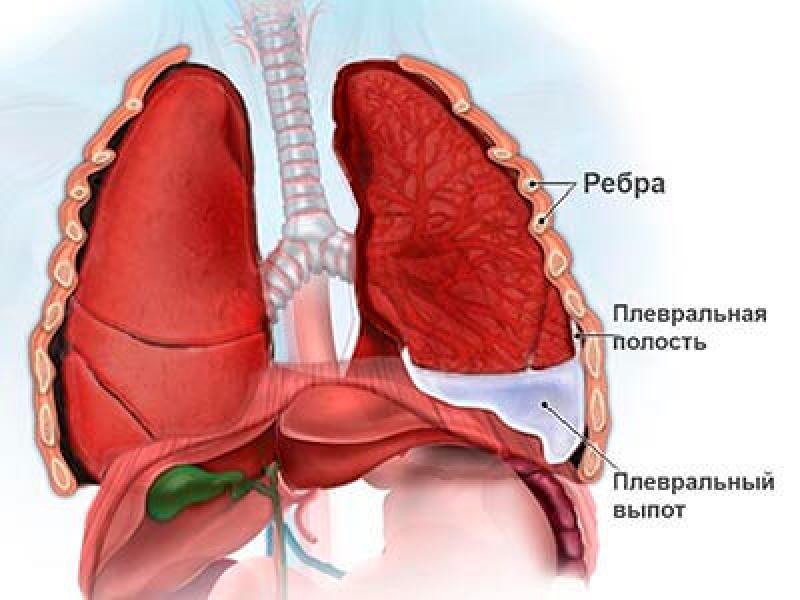

Симптомы и причины скопления воды в легких